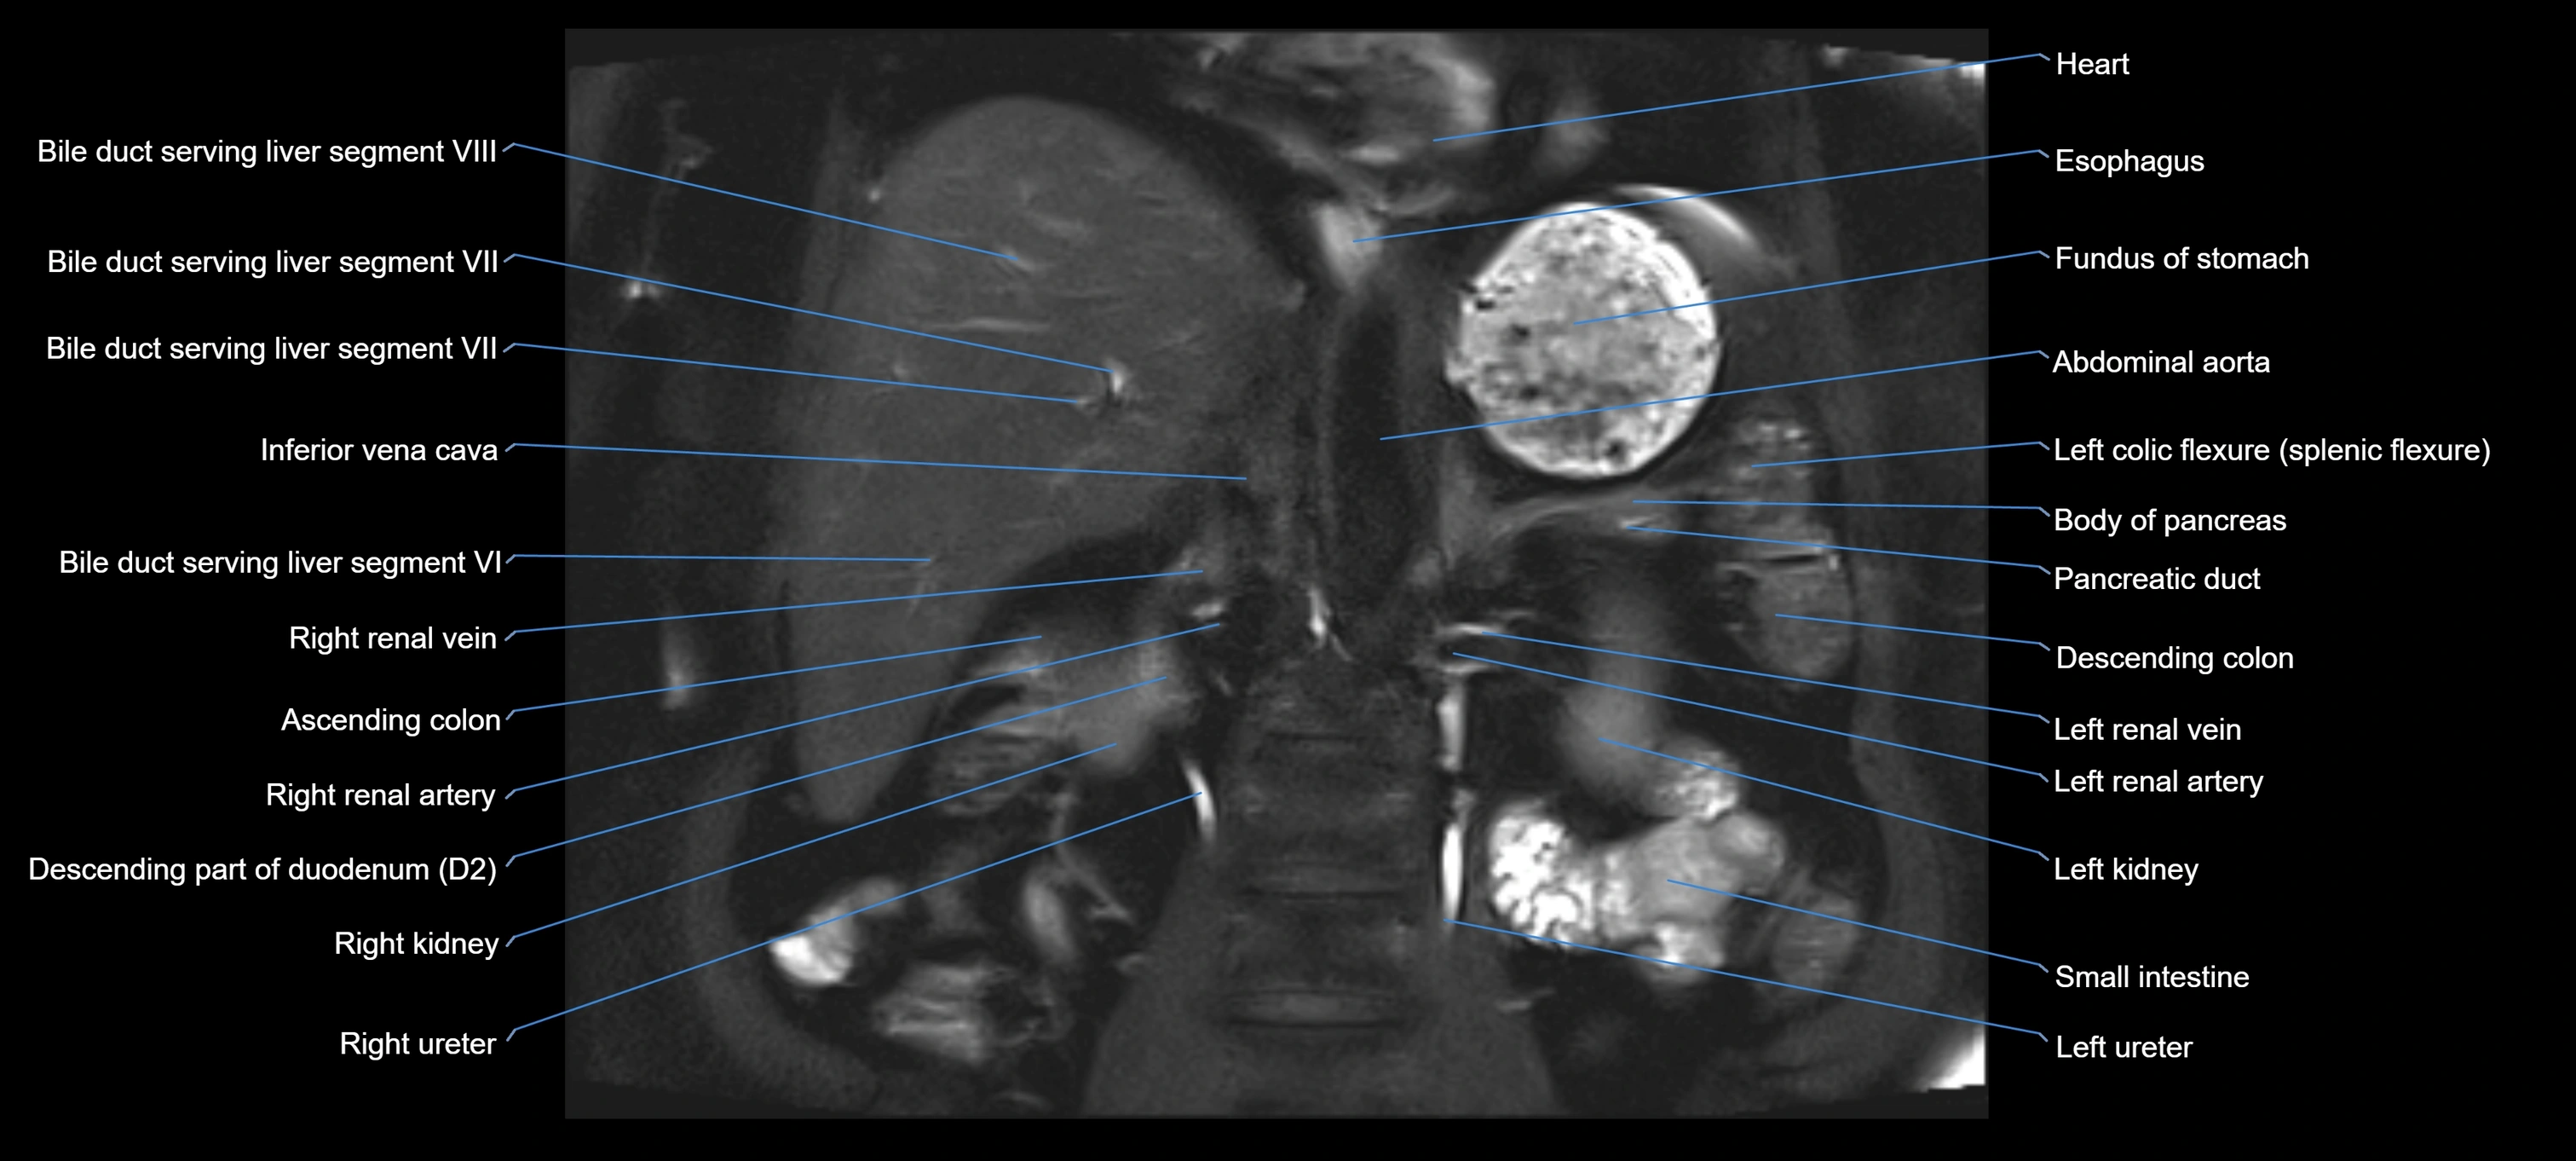

MRI image

image

Fullscreen Image